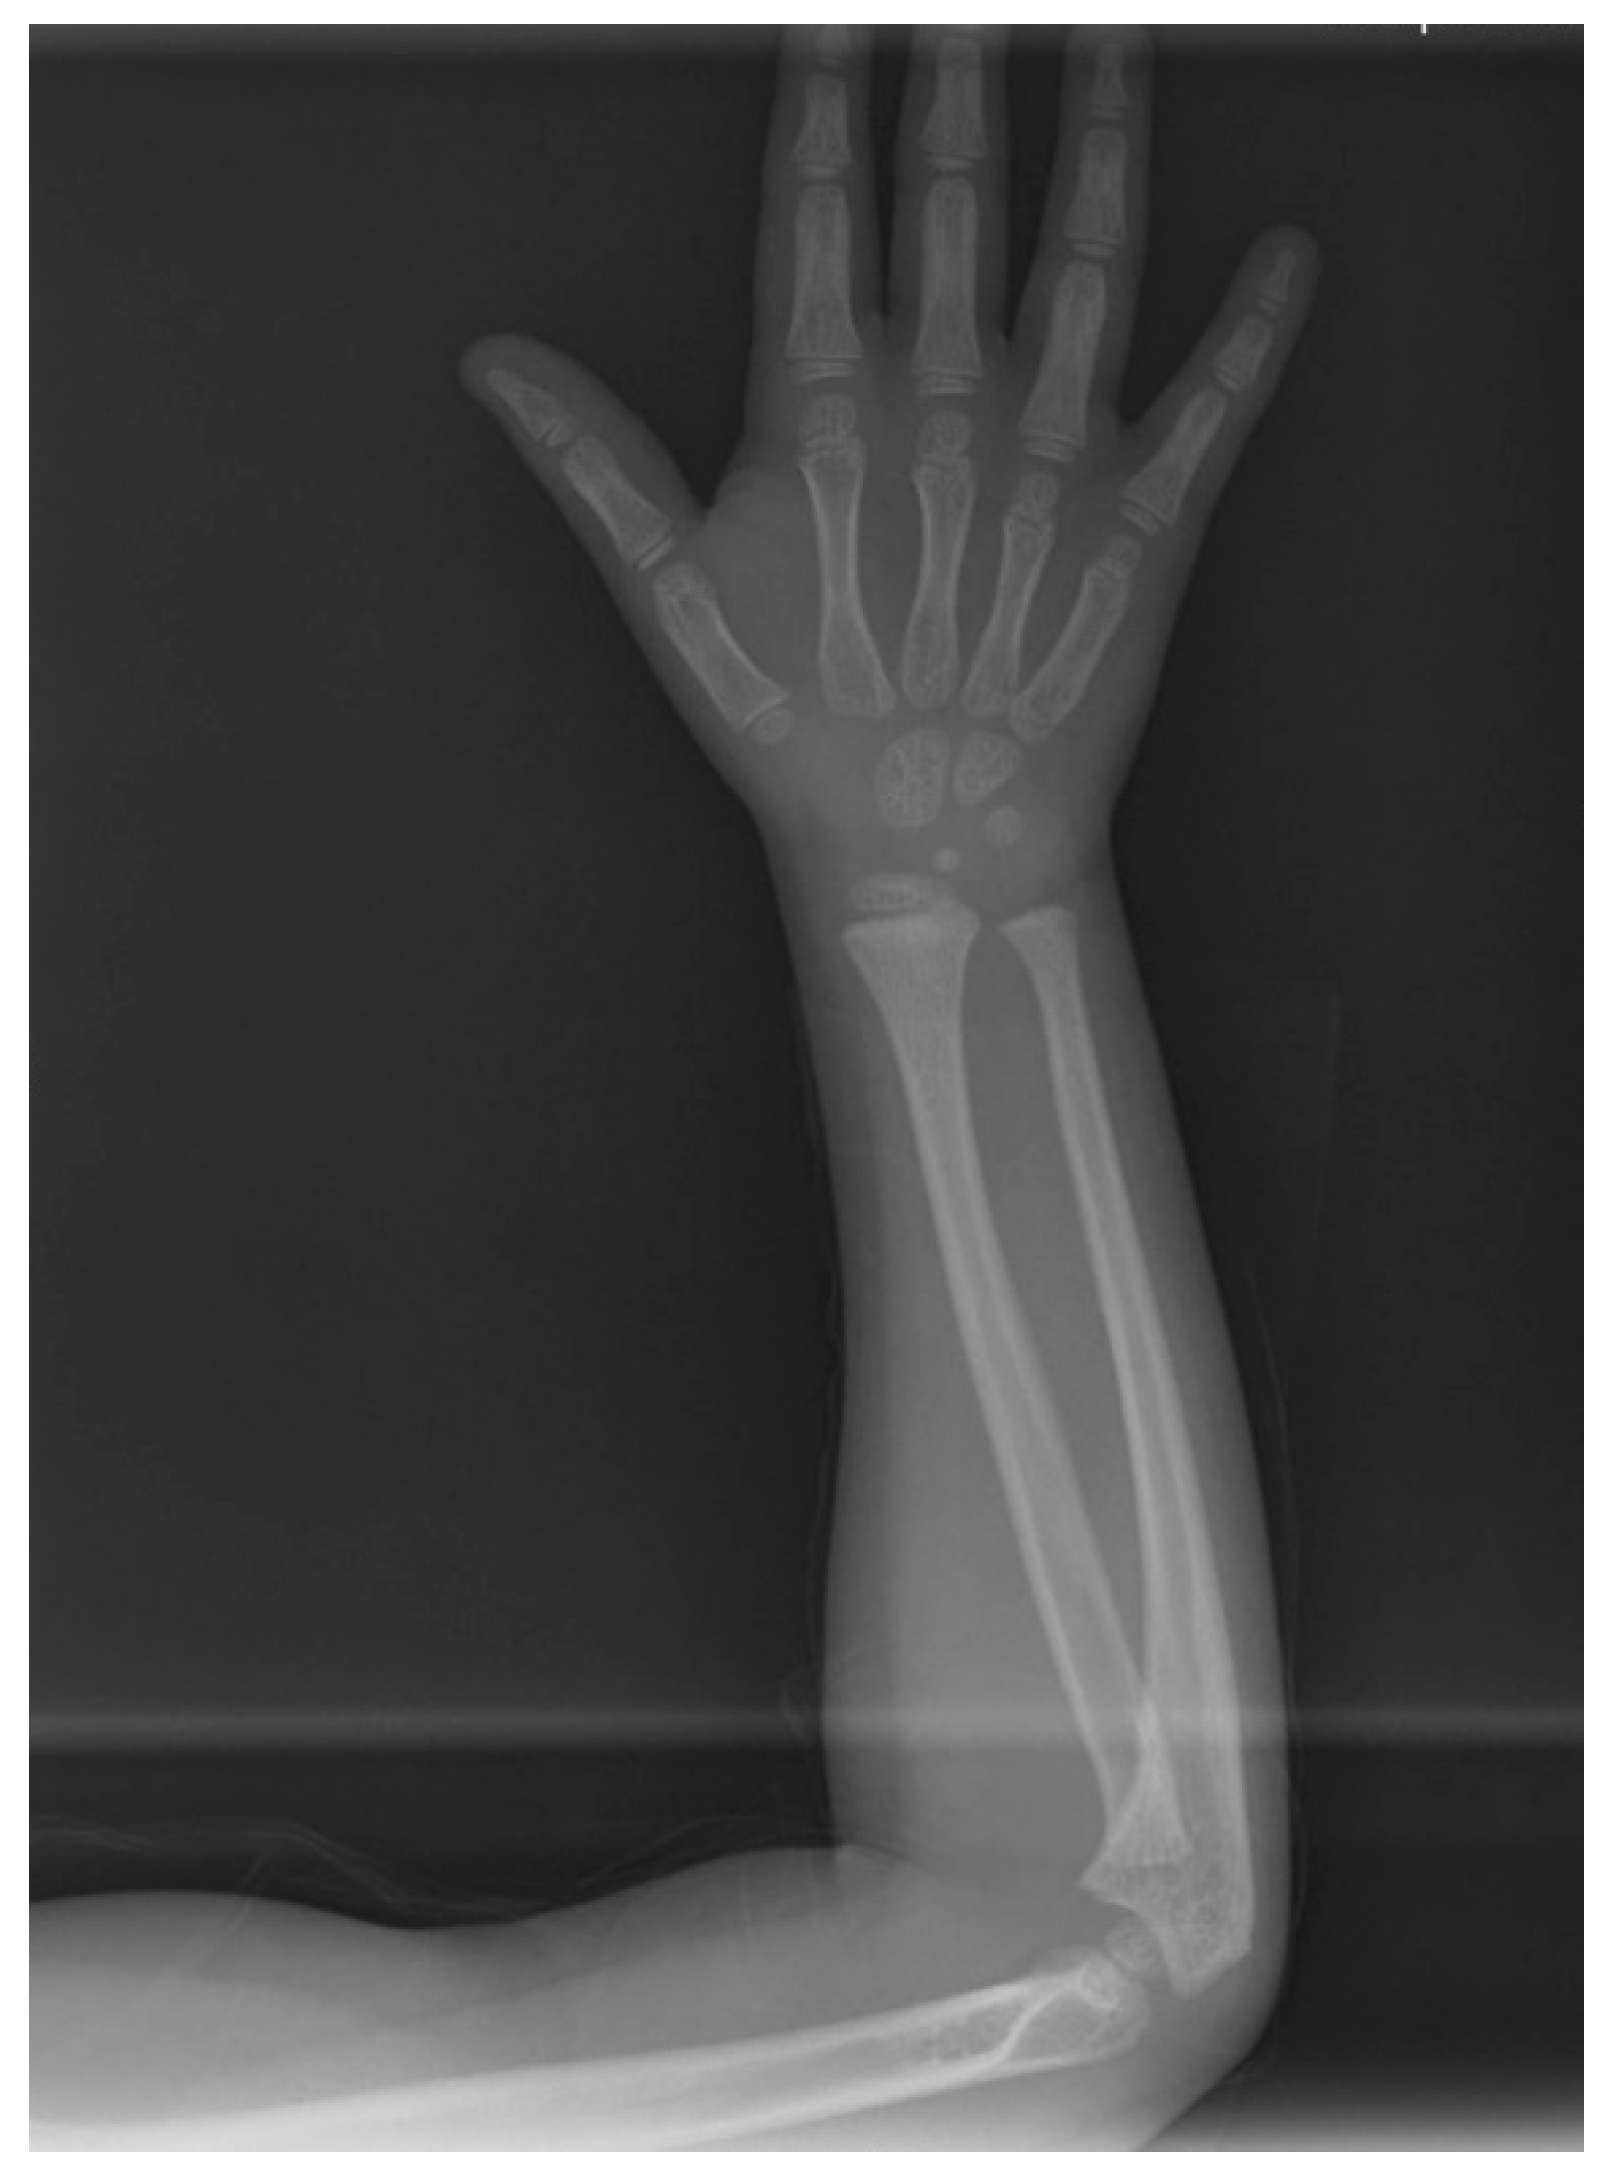

2. Case Presentation

2.1. Clinical Findings and Diagnosis